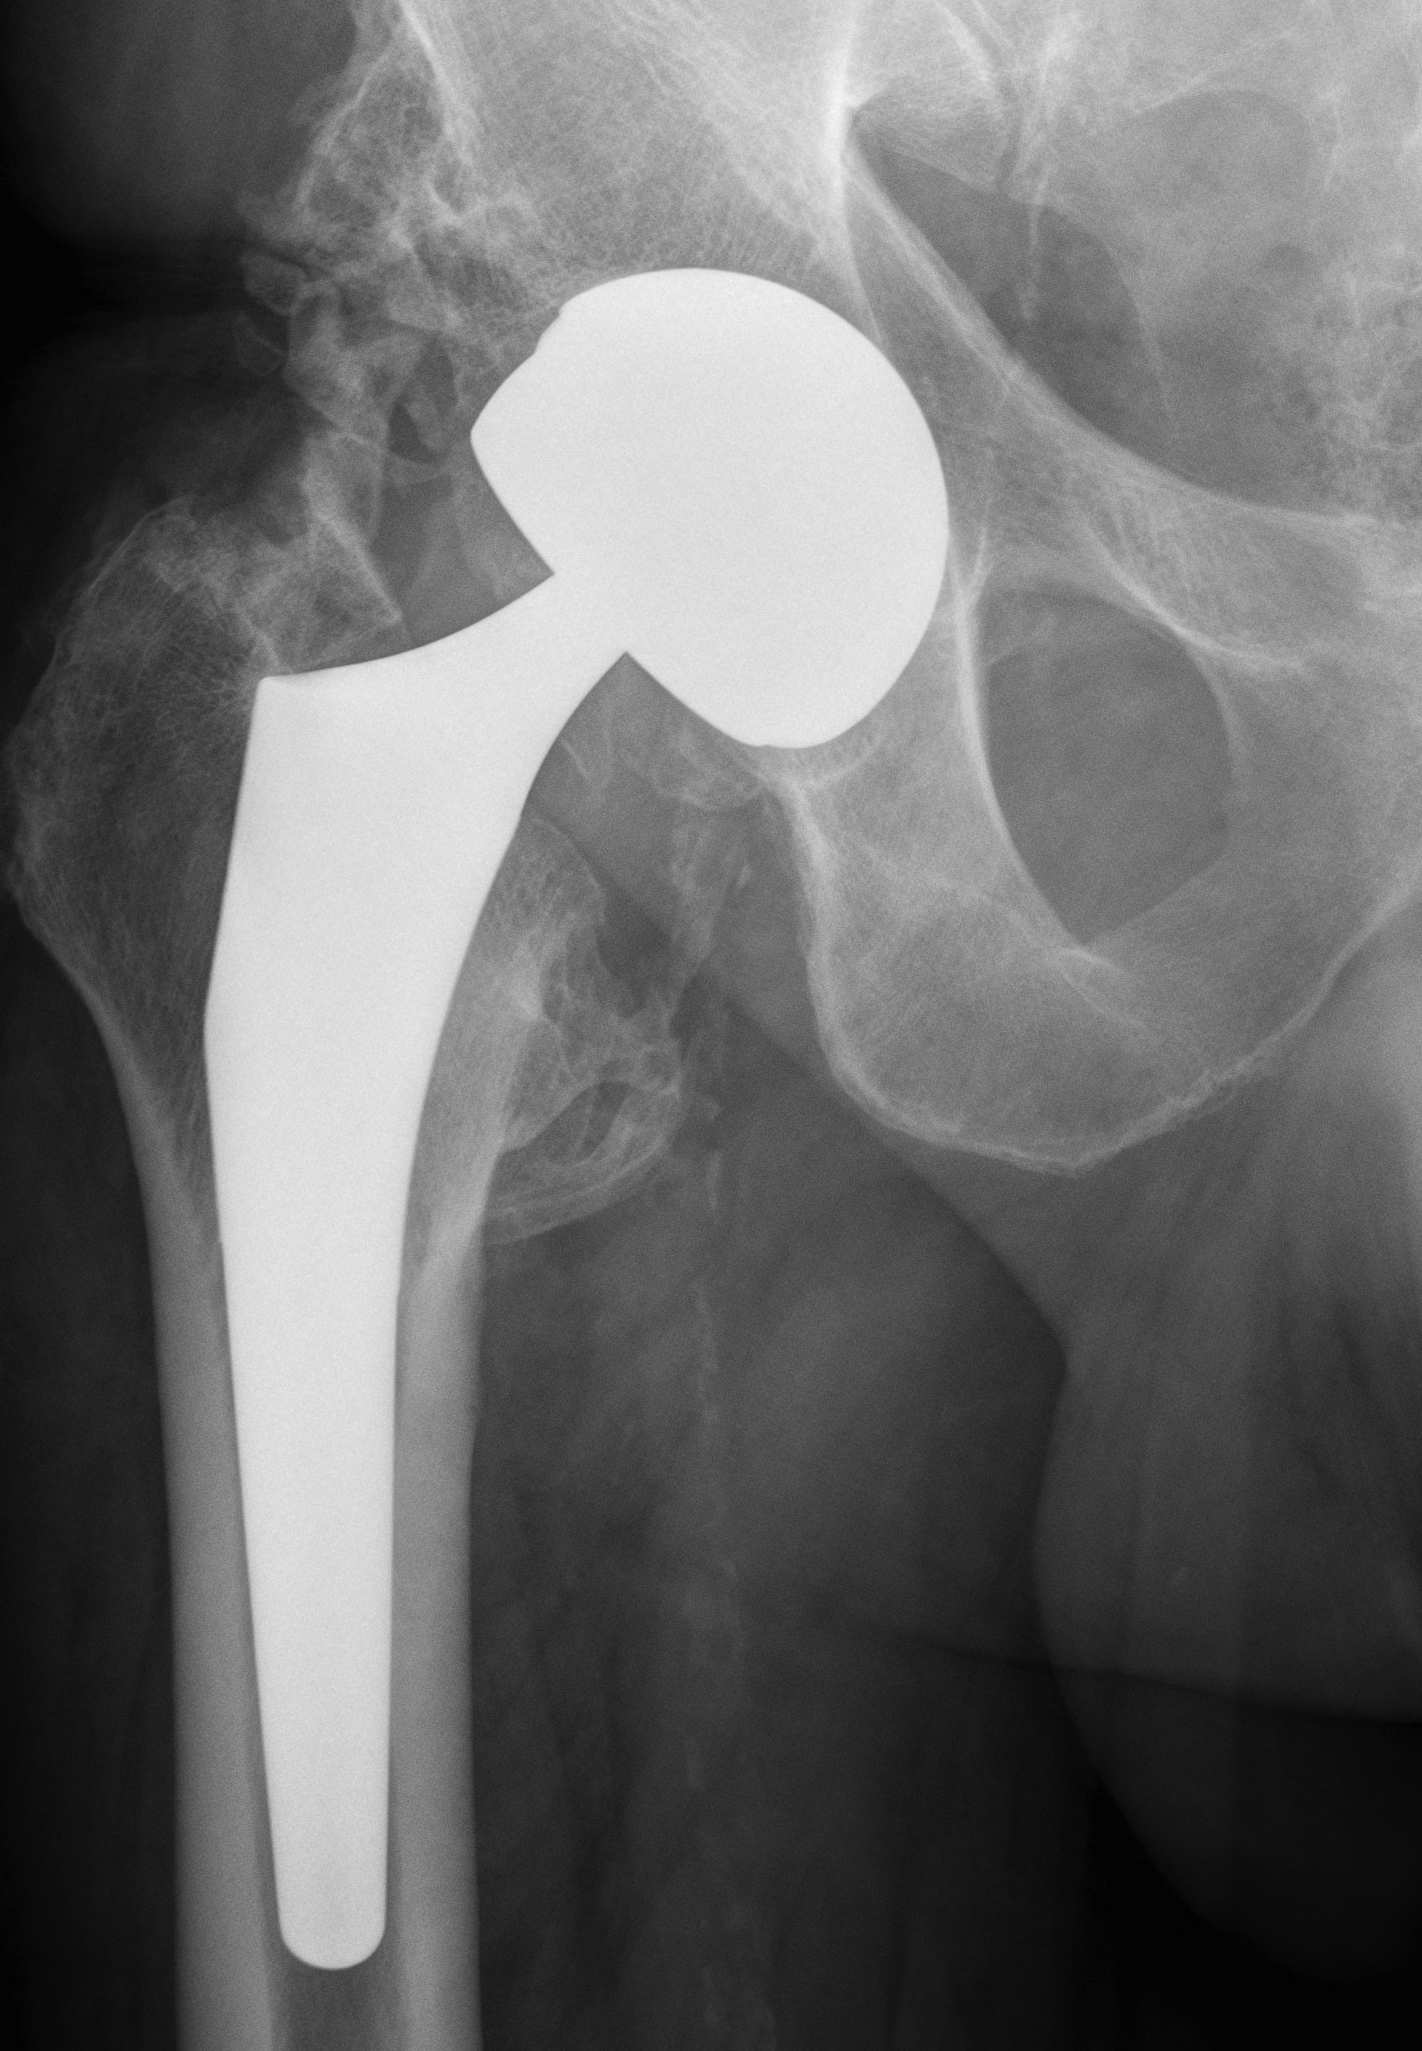

Reproduce the normal anatomical centre of rotation

Restore femoral offset

Maintain equal leg lengths

Usually template off normal hip

1. LLD

2. Offset

3. Femoral component

4. Acetabular component

5. Osteotomy / femoral seating